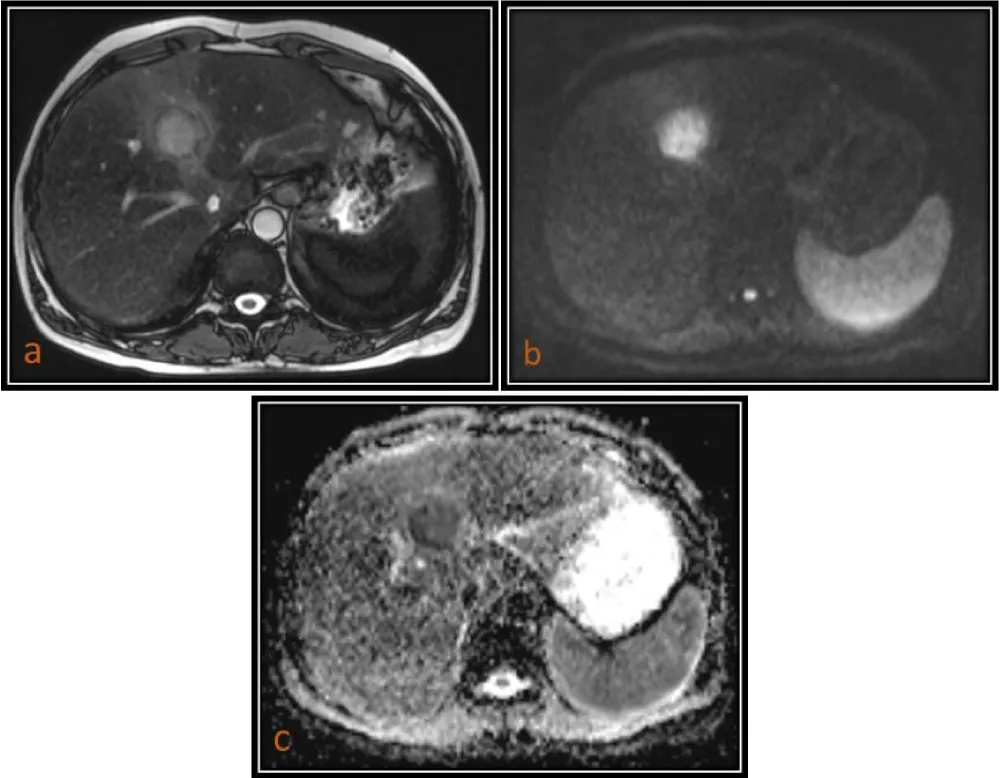

In our study, hepatic cysts demonstrated the highest ADC values, followed by hemangiomas, whereas malignant lesions such as HCC and metastases showed significantly lower ADC values. The mean ADC values of malignant lesions were significantly lower (0.90 ± 0.15 × 10-3 mm2/s) (Figures 1,2,4) than those of benign lesions (2.19 ± 0.29 × 10-3 mm2/s) (Figure 3), and this difference was statistically significant, in agreement with previous studies [10]. However, no significant difference was observed between primary (0.89 ± 0.15 × 10-3 mm2/s) and metastatic malignant lesions (0.90 ± 0.14 × 10-3 mm2/s), which may be attributed to the relatively small sample size.

Download Image

Figure 3: 63-year-old male patient with Liver hemangiomas. (a) Axial T2 (TruFISP)-weighted image shows two hyperintense lesions in the both lobes of liver which are hyperintense (T2 shine-through) on axial DW image (b = 800) as seen in (b), and remain hyperintense on ADC map with a high ADC value (1.846 x 10-3 mm2/s) as seen in (c) and shows peripheral puddling on T1 (VIBE) post contrast arterial phase images.